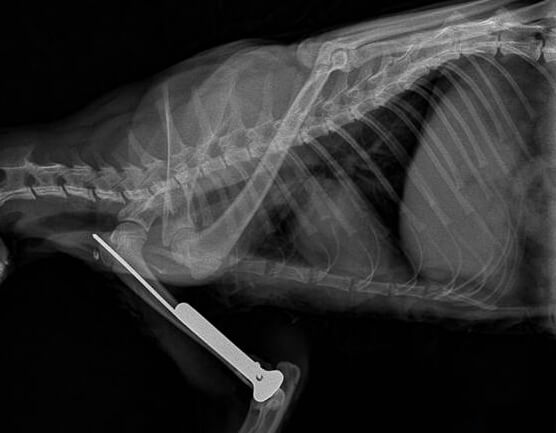

股骨粉碎性骨折

1.基础信息 家猫,年龄1岁,体重2.2kg,雄性,未绝育,从五楼坠落后无法站立和行走,主人带往我医院进行就诊。

2. 临床检查 患猫精神状态萎靡,口色苍白,T:38.3℃,P:86次/分,R:32次/分,呼吸急促,卧地不起,右前肢及双后肢解剖姿势异常,轻微牵引疼痛感明显,可闻及明显骨摩擦音。

4. 初步诊断 综合以上各项检查,初步诊断为右肱骨远端粉碎性骨折合并双侧腓骨远端骨折、双侧距骨粉碎性骨折。

5. 治疗 本病例胸腹部X线片检查未见明显异常,但鉴于患猫体况较差,术前3天给予输液预防继发感染、增加营养等,待患猫体况好转后,实施内固定手术。 丙泊酚诱导麻醉、异氟烷维持麻醉后,患肢备皮消毒。